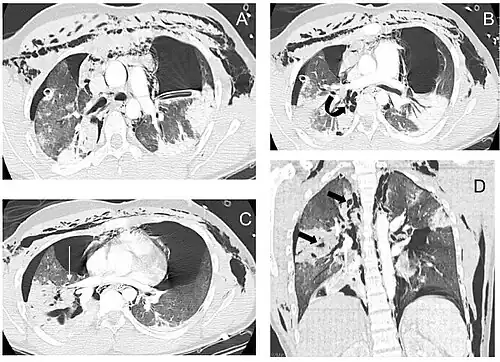

El diagnóstico y el tratamiento rápidos son importantes en la atención de la LCT;[6] si la lesión no se diagnostica poco después de producirse, el riesgo de complicaciones es mayor.[11] La broncoscopia es el método más eficaz para diagnosticar, localizar y determinar la gravedad de la LCT,[6][10] y suele ser el único método que permite un diagnóstico definitivo.[23] El diagnóstico con un broncoscopio flexible, que permite visualizar directamente la lesión, es la técnica más rápida y fiable.[8] En personas con LCT, la broncoscopia puede revelar que la vía aérea está desgarrada, o que las vías respiratorias están obstruidas por sangre, o que un bronquio se ha colapsado, ocultando de la vista bronquios más distales (inferiores).[3]

La radiografía de tórax es la técnica de imagen inicial usada para diagnosticar la LCT.[17] La radiografía puede no tener ningún signo en un paciente por lo demás asintomático.[15] Las indicaciones de LCT vistas en las radiografías incluyen deformidad en la tráquea o un defecto en la pared traqueal.[17] La radiografía también puede mostrar enfisema cervical, aire en los tejidos del cuello.[2] Las radiografías también pueden mostrar lesiones y signos acompañantes como fracturas y enfisema subcutáneo.[2] Si se produce un enfisema subcutáneo y el hueso hioides aparece en una radiografía a una altura inusual en la garganta, puede ser un indicio de que la tráquea ha sido seccionada.[4] También se sospecha de LCT si un tubo endotraqueal aparece en una radiografía fuera de lugar, o si su manguito parece estar más lleno de lo normal o sobresale a través de un desgarro en las vías respiratorias.[17] Si se desgarra un bronquio en toda su extensión, el pulmón puede colapsarse hacia fuera, hacia la pared torácica (en lugar de hacia dentro, como suele ocurrir en el neumotórax), porque pierde la unión al bronquio que normalmente lo mantiene hacia el centro.[6] En una persona tumbada boca arriba, el pulmón se colapsa hacia el diafragma y la espalda.[23] Este signo, descrito en 1969, se denomina signo del pulmón caído y es patognomónico de LCT (es decir, es diagnóstico de LCT porque no se produce en otras afecciones); sin embargo, sólo se produce en raras ocasiones.[6] Hasta en uno de cada cinco casos, las personas con traumatismo contuso y LCT no presentan signos de la lesión en la radiografía de tórax.[23] La TC detecta más del 90% de los TLC resultantes de traumatismo contuso,[3] pero ni la radiografía ni la TC sustituyen a la broncoscopia.[6]